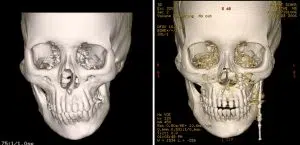

STAGES OF DISTRACTION OSTEOGENESIS

Distraction osteogenesis (DO) is a surgical method for gradually adjusting bone length or position through careful cutting and slow separation of fragments using a distraction device. Executed in stages, this procedure ensures proper bone healing.

Osteotomy: The initial stage involves surgically cutting the bone (osteotomy) with precision to achieve the desired lengthening or repositioning.